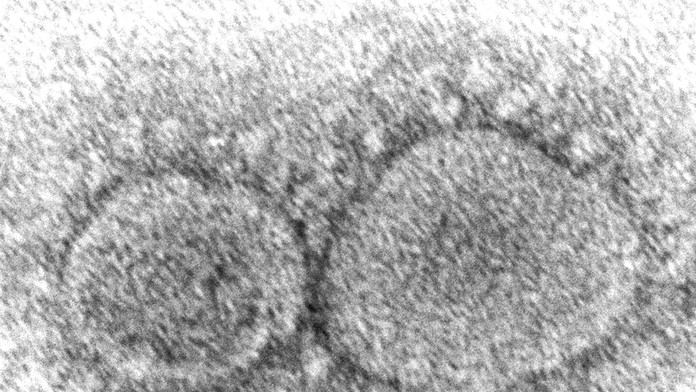

Archívna snímka z elektrónového mikroskopu z roku 2020, ktorú sprístupnilo Centrum pre kontrolu a prevenciu chorôb (CDC), zobrazuje nový koronavírus SARS-CoV-2. Zdroj: TASR/Hannah A. Bullock, Azaibi Tamin/CDC via AP